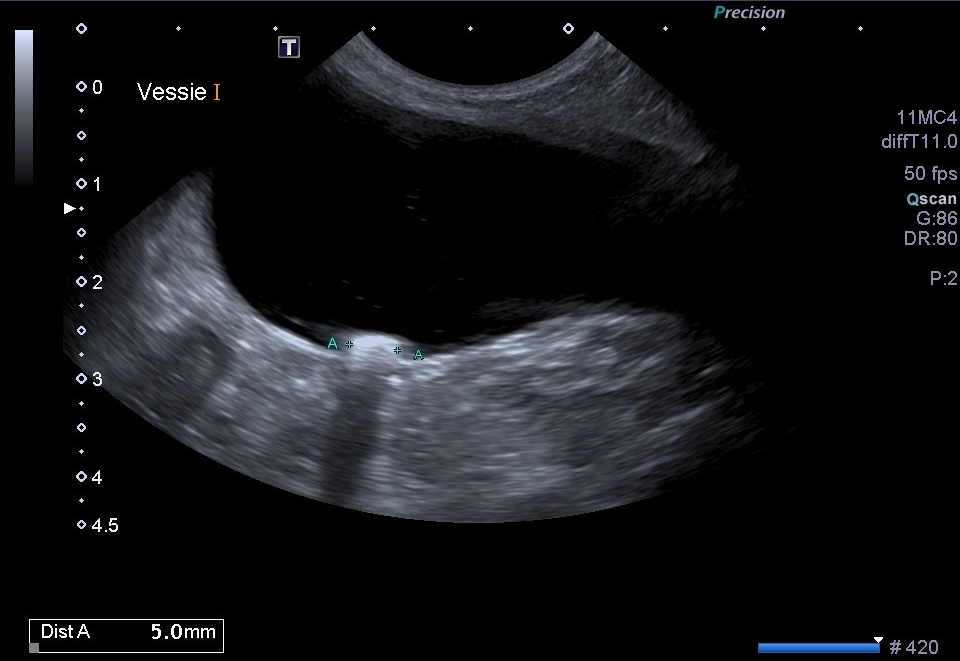

L’échographie est par ailleurs très souvent utilisée pour réaliser des examens complémentaires comme des ponctions ou des cystocentèses.

Échographieabdominale

Les échographies abdominales permettent de diagnostiquer des affections digestives, hépatiques, pancréatiques, uro-génitales, endocriniennes et tumorales.